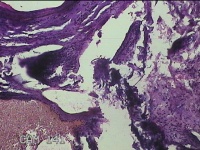

右拇指肿块

性别

女

年龄

73岁

临床诊断

右拇指肿物性质待查

一般病史

标本名称

大体所见

灰白粉红色肿物2.2x1.3x0.3cm一个,表面糜烂,切面灰白粉红色,质软。

图2